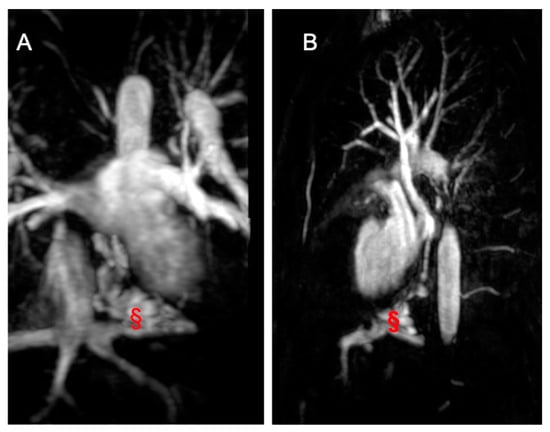

2.3. Coarctation of the Aorta